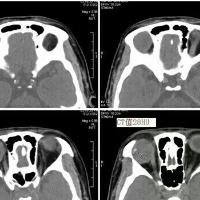

zxj320 3530天前或圆形肿块;同时累及眶内段、管内段及颅内段可表现为“哑铃形。

zxj320 3577天前显示病变区呈半圆形或扁平形。常合并邻近眼外肌增厚或眼环增厚。